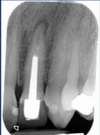

83

is the following periapical pathology or not?

yes - root filled - PDL isnt continuous - lamina dura isnt continuous